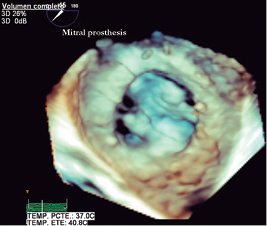

Transthoracic and transesophageal echocardiography: left ventricular end-diastolic volume of 45 milliliters, systolic volume of 11 milliliters, ejection fraction 76%, without changes in global or segmental mobility at rest, without thrombi, with concentric remodeling data; dilated left atrium without thrombi, a left atrial volume index (LAVI) 48 mL/m2 is calculated; mitral valve bio-prosthesis thickened, heavily calcified, irregular by pannus (Figure 3), with inadequate excursion and closure, with one of the leaflets fixed (Figure 4), an acceleration of flow rate 2.9 m/s, it shows maximum peak velocity of 2.9 m/s with maximum gradient of 34 mmHg and mean gradient of 25 mmHg (Figure 5), valve area by continuity 0.5 cm2, indexed 0.3 cm/m2, by pressure half-time of 0.7 cm2, with mild central regurgitation jet, Doppler index of 4; aortic valve bio-prosthesis with mild calcification, with suitable excursion and closing, maximum peak velocity of 2.2 m/s, maximum gradient 29 mmHg, mean gradient 15 mmHg, valve area by continuity 1.3 cm2, indexed 0.81 cm/m2, with no evidence of leakage, a Doppler index of 0.28; right ventricle: dilated, hypertrophic, with preserved systolic function, tricuspid annular plane systolic excursion (TAPSE) 17 mm/m2, S wave 12 cm/s; right atrium: dilated, without thrombi; tricuspid valve: structurally normal, deficient coaptation, with a concentric regurgitation jet generating severe failure, vena contracta 10 mm, regurgitation area 16 cm2, a systolic pulmonary artery pressure (SPAP) of 105 mmHg is calculated.

Figure 3: Transesophageal echocardiogram with three-dimensional reconstruction of the mitral bio-prosthesis Carpentier-Edwards #27 (Edwards Lifesciences), degenerated, seen from the left atrium.

Figure 4: Transesophageal echocardiogram: showing the null mobility of the posterior leaflet (arrows), determining an incomplete opening in diastole (A and C). In systole the mitral prosthesis shows significant thickening of one of its valves (B and D).